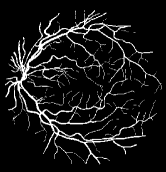

Refer to caption

Figure 1: Vessel segmentation results of side-output(s-out) layers produced by three networks. From top to bottom the network is normal DSN (with no short connections), BS-DSN (DSN with bottom-top short connections) and BTS-DSN (DSN with both bottom-top and top-bottom short connections), respectively.

As pointed out in recent works [15, 17], a good semantic segmentation network should learn multi-level features. Further, it should have multiple stages with different receptive fields to learn more inherent features from different scales. FCN, taken as an example, uses skip connections to fuse multiple stages outputs, as well as the HED network, in which a series of side-output layers are added after each stage in VGGNet. The HED network was first proposed for edge detection, and further used for image-level vessel segmentation in recent studies [6, 16], with significant performance. However, our experimental results show that such network architecture is not appropriate for vessel segmentation directly. Figure 1 provides such an illustration. Reasons for this phenomenon are straightforward. On one hand, the side-output of the first layer often contains too many noises. On the other hand, the features produced by the last side-output layer are too coarse due to information loss of pooling operation. Obviously, the inaccurate vessel map of side-output1 and side-output4 should have negative impacts on the final segmentation result.

In addition, we can observe from Figure 1 that the side-output1 and side-output4 of the BTS-DSN were more accurate compared with those of the DSN.